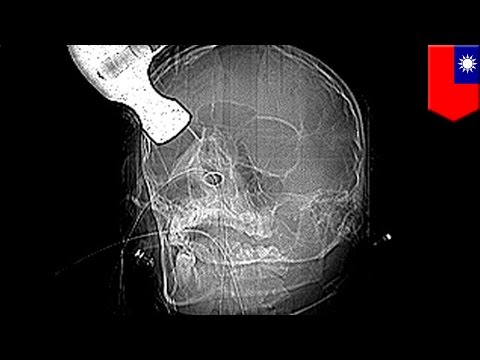

Attempted hammer murder: Security guard tries to bash in accountant’s head